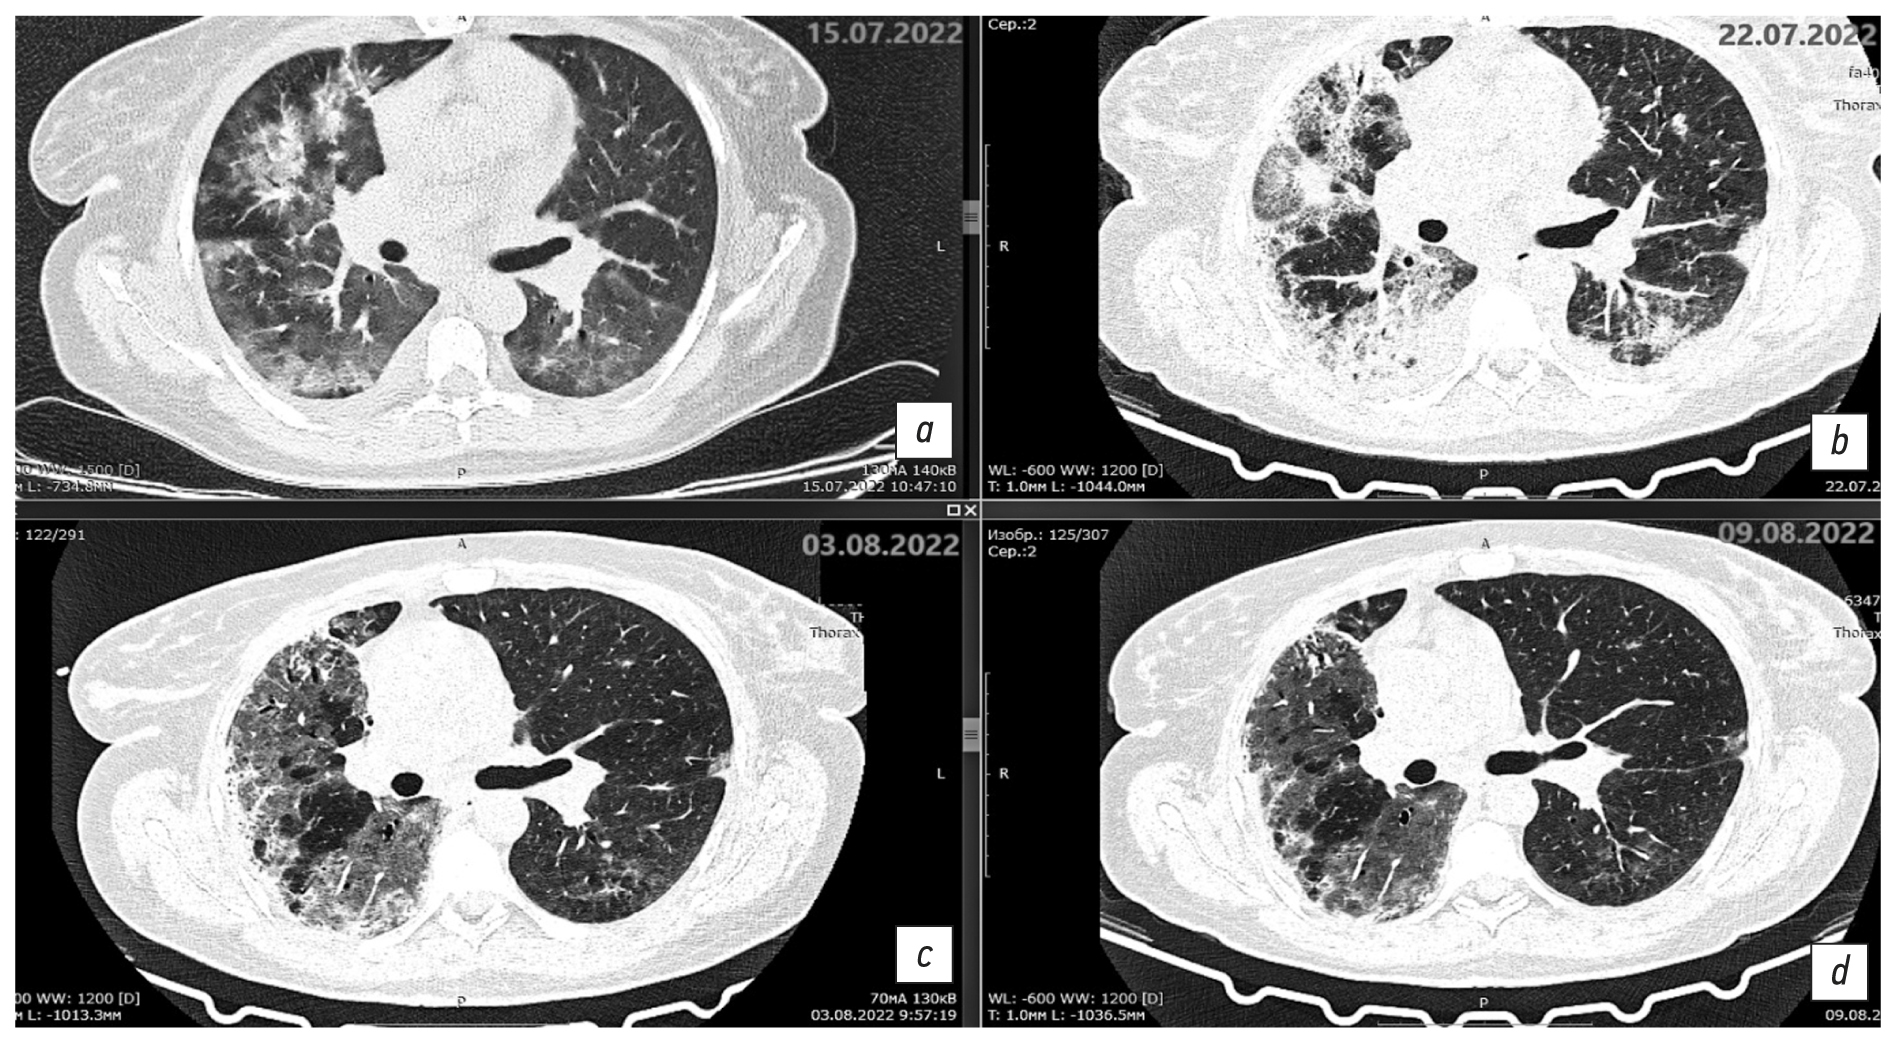

Fig. 1. Axial sections at the level of the aortic arch, pulmonary window. Changes in the areas of heterogeneous infiltration: a: chest CT scan dated July 15, 2022, day 11 of the disease, day 1 of hospitalization; b: chest CT scan dated July 22, 2022, day 18 of the disease, day 7 of hospitalization; c: chest CT scan dated August 3, 2022, day 30 of the disease, day 19 of hospitalization; d: chest CT scan dated August 9, 2022, day 36 of the disease, day 25 of hospitalization.

Fig. 2. Axial sections at the level of the main bronchi, pulmonary window. Changes in the areas of heterogeneous infiltration: a: chest CT scan dated July 15, 2022, day 11 of the disease, day 1 of hospitalization; b: chest CT scan dated July 22, 2022, day 18 of the disease, day 7 of hospitalization; c: chest CT scan dated August 3, 2022, day 30 of the disease, day 19 of hospitalization; d: chest CT scan dated August 9, 2022, day 36 of the disease, day 25 of hospitalization.

Fig. 3. Axial sections at the level of the basal parts of the lungs, pulmonary window. Changes in the areas of heterogeneous infiltration. a: chest CT scan dated July 15, 2022, day 11 of the disease, day 1 of hospitalization; b: chest CT scan dated July 22, 2022, day 18 of the disease, day 7 of hospitalization; c: chest CT scan dated August 3, 2022, day 30 of the disease, day 19 of hospitalization; d: chest CT scan dated August 9, 2022, day 36 of the disease, day 25 of hospitalization.

Description of the chest CT scan dated July 15, 2022 (Fig. 1a, 2a, 3a): The lungs are fully expanded. Pneumatization is diffusely reduced. The pulmonary pattern is deformed. Both lungs show multifocal infiltrative changes of the pulmonary parenchyma of a ground-glass type with reticular shadows and peribronchial consolidation type. The infiltrative changes are located randomly. The parenchyma is visibly involved. Up to 30% and 60% of the pulmonary parenchyma is affected in the left upper and lower lobes, respectively. Up to 60% of the pulmonary parenchyma is affected in the right upper and lower lobes. The volume of the affected parenchyma in the left lung is up to 45% and less than 70% in the right lung. The total percentage of lung damage reaches 70%. The degree of severity is at the CT3 level.

The configuration and lumen of the trunk bronchi are unremarkable. The mediastinum is of normal shape and location. A layer of free fluid, up to 20 mm in thickness, is observed in the upper aortic pouch. The intrathoracic lymph nodes are indurated and enlarged. The para-aortic group is 11 mm along the short axis, the paratracheal group is up to 12 mm, the bifurcation group is up to 17 mm, and both bronchopulmonary groups are up to 12 mm. The major vessels are of normal structural organization and sizes. In both pleural cavities, a layer of free fluid is observed, measuring up to 15 mm along the posterior wall on the right side and up to 5 mm on the left side. Results: Bilateral multifocal pneumonia, intermediate probability of COVID-19 pneumonia (pneumonia of other etiology?), CT3, 65%–70%. Enlarged mediastinal lymph nodes, hydropericardium, bilateral hydrothorax, and focal mass in the left breast.

On day 18 of the disease and day 7 of the hospital stay, the chest CT scan dated July 22, 2022 (Fig. 1b, 2b, 3b) revealed negative changes in bilateral multifocal pneumonia and weakly negative changes in bilateral pneumothorax and hydropericardium. Moderate intrathoracic lymphadenopathy without changes and a focal mass in the left breast were observed. Antibiotic therapy was re-adjusted; rifampicin was discontinued, and intravenous tigecycline 100 mg daily was added to levofloxacin 1 g daily. This regimen demonstrated gradual positive changes.

Since August 1, 2022 (day 28 of the disease, day 17 of inpatient treatment), the patient’s condition was of average severity, with normalized body temperature, decreased symptoms of respiratory insufficiency, and persistent weakness. The air saturation was 89% and 97% with humidified insufflation at 4 L/min. The chest CT scan dated August 3, 2022 revealed mixed changes of bilateral multifocal pneumonia. The left lung exhibited positive findings, whereas the right lung displayed cavitary lesions. The presence of a dilated bronchial lumen and heterogeneous infiltration were suspected. The regression of bilateral hydrothorax was accompanied by negative changes in hydropericardium.

Description of the chest CT scan dated August 3, 2022 (Fig. 1c, 2c, 3c): The lung volume increased due to regression of fluid in the pleural cavities on both sides. Previously, the maximum fluid level was 21 mm on the right side and up to 19 mm on the left side, with a flow along the interlobular pleura up to 17 mm. Multiple segments of the lungs exhibit extensive confluent areas of heterogeneous infiltration, predominantly of the consolidation type. Within these areas, the lumen of dilated bronchi and a ground glass appearance is observed, accompanied by a single discoid atelectasis. The changes have no preferred localization. A marked continuous reduction in the extent and intensity of changes in the left lung is observed, with preserved ground-glass changes and consolidation (S1/2).

The extent of changes in the right lung remains unaltered. However, an increase in consolidation is observed in the upper regions. Additionally, heterogeneous infiltration in the right lung in S6 and S10 segments caused cavitary lesions up to 9 × 7 mm and 4 × 5 mm, respectively. This phenomenon is likely attributable to the dilation of the bronchial lumen, heterogeneous expansion of infiltration, or the formation of a destruction cavity.

The paratracheal lymph nodes are 12 mm in diameter, whereas the bifurcation lymph nodes measure up to 14 × 18 mm (previously 17 × 22 mm). The heart is unremarkable. Fluid in the pericardial cavity supradiaphragmatically is up to 14 mm (previously 10 mm). A focal mass is present in the upper-inner quadrant of the left breast, measuring up to 11 mm, with a density of 22 HU, and insufficiently clear contours. Results: Bilateral multifocal pneumonia with mixed changes (positive in the left lung). Cavitary lesions in the right lung may be characterized by dilated bronchial lumen, heterogeneous infiltration, or a destruction cavity. Follow-up chest CT is recommended. There is evidence of bilateral hydrothorax regression. The hydropericardium shows negative changes. Moderate intrathoracic lymphadenopathy exhibits weakly positive changes. A focal mass in the left breast is observed.

The antibiotic therapy was continued at the same dosage, prophylaxis of thromboembolic events was administered, and periodic oxygen therapy was provided.

On August 10, 2022 (day 37 of the disease, day 26 of hospitalization), the patient’s condition was deemed satisfactory. The patient reported a rare dry cough and slight exertional dyspnea. The patient’s air saturation was 97%. The chest CT scan dated August 9, 2022 (Fig. 1d, 2d, 3d) demonstrated positive changes in bilateral multifocal pneumonia, with a decrease in intensity. Additionally, there were no changes in cavitary lesions in the right lung, which could be attributed to dilated bronchial lumen or heterogeneous infiltration. Hydropericardium also showed positive changes.